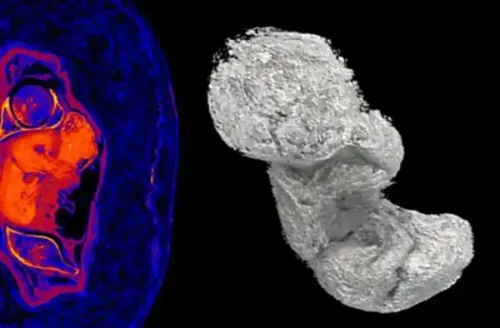

Nonostante il nome maschile trovato sul sarcofago, i ricercatori – durante una prima indagine, anch’essa non invasiva – avevano riscontrato la mancanza dell’organo maschile che veniva mummificato con il resto del corpo. Ulteriori indagini, svolte con la Tac e con i più avanzati strumenti di diagnostica avevano permesso di svolgere virtualmente le bende e di scoprire il corpo di una giovane donna. Altre ricerche hanno consentito di vedere il corpo del bambino e di conoscere le sostanze che furono utilizzate per la mummificazione.

La Tac, attraverso la misurazione del feto – ha consentito di stabilire che la donna era incinta da 28 settimane e pertanto era entrata nel settimo mese di gravidanza. Il settimo mese di gravidanza è infatti compreso tra le 26 settimane+3 giorni e le 30 settimane+4 giorni.

Alla 28esima settimana il peso del feto è in media 875 grammi ed è lungo circa 36 cm. In questa fase della gravidanza i polmoni dei bambini stanno per completare il loro sviluppo e i movimenti respiratori sono ben coordinati.

«Per ragioni sconosciute il feto non è stato rimosso dagli imbalsamatori, ma non è stato possibile determinarne il sesso» ha detto Wojciech Ejsmond, dell’Istituto delle culture mediterranee e orientali dell’Accademia polacca delle scienze. «La scoperta apre nuovi orizzonti su tecniche e aspetti ancora sconosciuti delle sepolture egizie». In un nuovo studio pubblicato sul “Journal of Archaeological Science”, Ożarek-Szilke, co-direttore del Warsaw Mummy Project, ha spiegato che la defunta era stata coperta di Natron per asciugare i liquidi del corpo. Il Natron è una miscela naturale contenente carbonato di sodio decaidrato e circa il 17% di bicarbonato di sodio, più cloruro di sodio e solfato di sodio. All’interno del corpo della giovane donna, il passaggio da ambiente alcalino ad ambiente acido ha causato la lisciviazione di minerali dalle ossa fetali, che hanno cominciato a disseccarsi e mineralizzarsi.